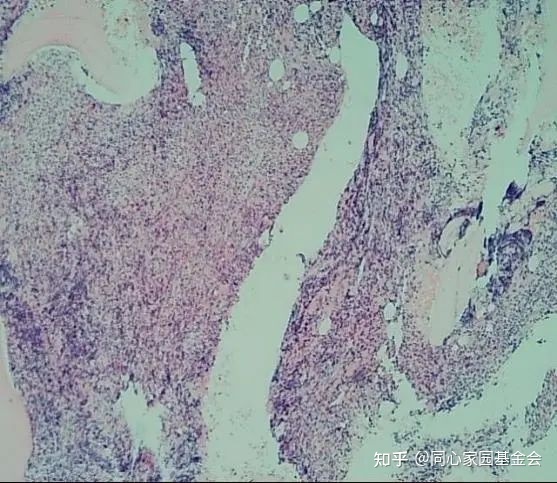

骨髓活检报告如图3-4:镜下描述:骨髓有核细胞增生过度(造血面积占约95%);粒/红比例增高;粒系增生,以较成熟阶段细胞为主,偏幼稚细胞散在少见;红系以中晚幼红细胞为主;巨核细胞散在易见,易见核深染、畸形、分叶少巨核细胞,部分呈“气球样”;淋巴细胞散在可见;浆细胞偶见;骨髓间质可见网状纤维增生。免疫组化:CD34幼稚细胞偶见(+);CD68幼稚细胞偶见(+);CD61巨核细胞(+)。符合原发性骨髓纤维化——纤维化前期(Pre-PMF),请结合临床及其它相关检查等。

图4 骨髓活检H-E染色40倍

注:1、原幼细胞比例小于5%;2、MF-1级;3、未见明显的胞体大、分叶多的巨核细胞,未见“鹿角状”巨核细胞;4、巨核细胞簇状、散在多见,易见核深染、畸形、分叶少巨核细胞。JAK2基因V617F突变定量检测(Q-PCR)结果:阳性。